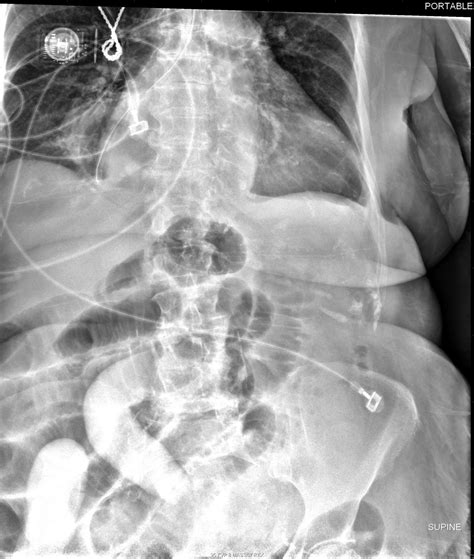

• X-Ray Imaging: A series of X-ray images are taken at regular intervals as the barium moves through the small intestine. This allows radiologists to observe the movement and structure of the small intestine.

• Small Bowel Obstruction: A blockage in the small intestine that prevents the normal passage of digestive contents.

• Transit Time: The time it takes for the barium to pass through the small intestine, which can be affected by conditions like obstruction or motility disorders.

• Structural Abnormalities: Any visible abnormalities such as strictures, fistulas, or masses that may indicate disease.